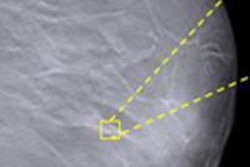

This week's study assessed the short-term outcomes of screening mammography using CAD by measuring the difference in detection rates for invasive cancer and ductal carcinoma in situ (DCIS) between sites using CAD and those that didn't. The theory is that if CAD is detecting more cases of DCIS, it could be a sign that the technology is contributing to "overdiagnosis" by finding cancers that may not prove to be a threat during a woman's lifetime.

The team found that use of the technology was associated with greater DCIS incidence but no difference in invasive breast cancer incidence. A woman receiving mammography screening at a site using CAD had a higher adjusted odds ratio, 1.17, for receiving a diagnosis of DCIS compared with those screened at sites without CAD (p < 0.001).